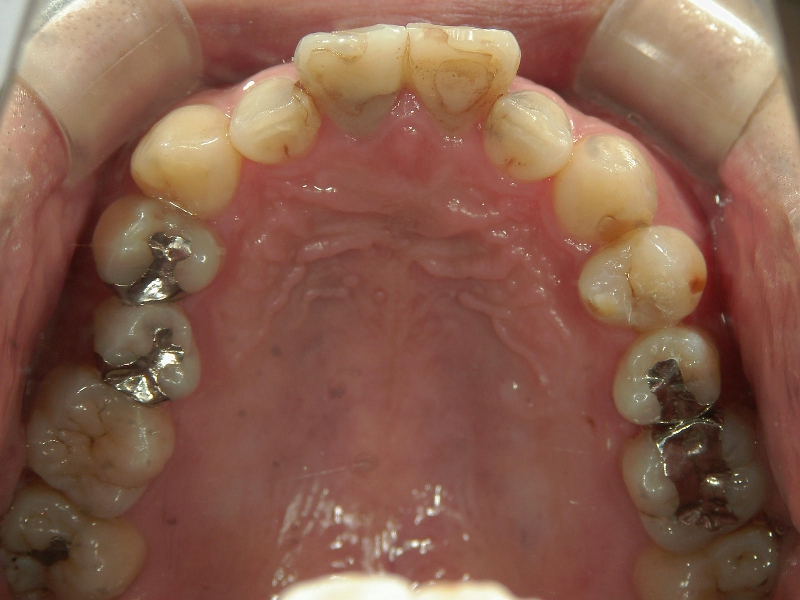

矯正歯科 治療前 上顎の左右4番計2本を抜歯し叢生を改善。

矯正_灰色.pngno.24_8228_治療前_上.jpg矯正_灰色.png